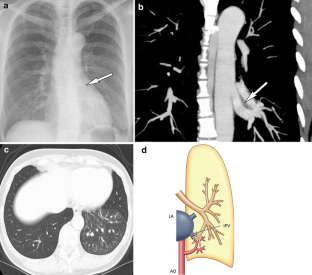

Congenital lung malformations (CLM) comprise a broad spectrum of maldevelopment that spans a continuum of maldevelopment involving parenchyma, bronchi, and vasculature. They may present as respiratory symptoms at birth and can be the source of morbidity and mortality. Early diagnosis is important for adequate therapy to prevent complications, such as recurrent infections, or to help normal lung development. Prenatal diagnosis of CLM using ultrasound (US) and magnetic resonance imaging (MRI) has increased, but chest radiography and computed tomography (CT) still play important roles in making diagnosis. This article reviews the clinical and radiographic features of various CLM.